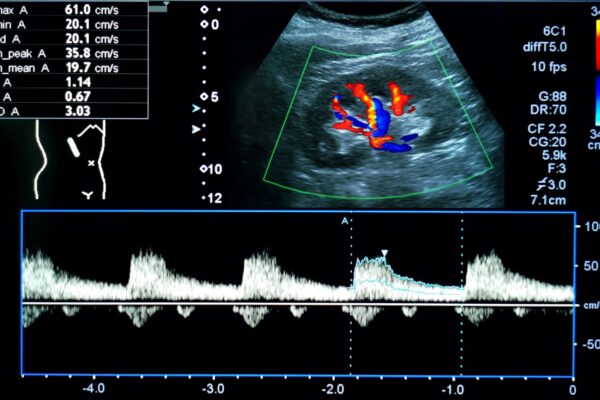

Duplex- und Dopplersonographie

Duplex- und Dopplersonographien sind spezielle Ultraschalluntersuchungen, mit denen Arterien und Venen, also Blutgefässe, beurteilt werden können. Der Schallkopf sendet Wellen in einer bestimmten Frequenz aus, die Wellen werden von den Blutkörperchen und den Gefässwänden in einer veränderten Frequenz reflektiert. Diese Veränderungen der Frequenzen hängen u.a. von der Bewegung der Blutkörperchen ab. Dadurch kann die Richtung des Blutflusses und die Fliessgeschwindigkeit des Blutes bestimmt werden. Dem Arzt ist es dadurch möglich, Einengungen (Stenosen) oder Verschlüsse von Blutgefässen zu erkennen. Die Methode ist völlig risikofrei und eignet sich zur Untersuchung sämtlicher Blutgefässe am Hals, an den Extremitäten (Arme und Beine) sowie im Bauchraum.

- Venenthrombosen an den Beinen (Venenverstopfung durch Blutgerinnsel)

- Arteriosklerose (Gefässverkalkungen durch Ablagerungen von Kalk und Fetten in den Arterien) zB bei den Halsgefässen zur Vorbeugung eines Hirninfarktes